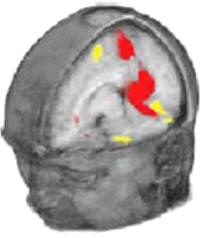

Con la nueva tecnología informática, las imágenes obtenidas por scanners PET y MRI muestran donde exactamente ocurren los cambios en flujo sanguíneo dentro del cerebro

También se pueden examinar otros fenómenos tales como la percepción, el aprendizaje, los recuerdos, el pensamiento e incluso la planificación. A menudo, se designan dos tareas teniendo que realizarse una justo después de la otra. La idea es que la primera tarea es la que implica el proceso en que el investigador está interesado mientras que la otra no debería. La sucesión de imágenes que se obtienen se substraen la una de las otras para obtener una imagen en 2 dimensiones, con los cambios que están específicamente asociados con el proceso cerebral realizado. Estas imágenes son acumuladas y apiladas por el ordenador para crear una substracción efectiva y proporcionar una imagen en 3 dimensiones (ver el dibujo de la página anterior). Los recientes avances y descubrimientos hacen que incluso breves pensamientos o cortos procesos cerebrales (tan cortos como uno o dos segundos) puedan ser analizados. Esto es lo que se conoce como MRI asociado a un proceso.

Para determinar si los cambios en una señal son reales y estadísticamente significativos durante la realización de una tarea se utilizan sofisticados métodos de análisis de datos. Un sistema de análisis que ha permitido estandarizar el procesado de los datos obtenidos de las imágenes es el llamado Mapeo parametrito estadístico (SPM). Los mapas SPM normalmente son en color, en donde el amarillo intenso se usa para las áreas de mayor actividad (“calientes”) mientras que el azul y negro indican áreas de menor actividad (“frías”).